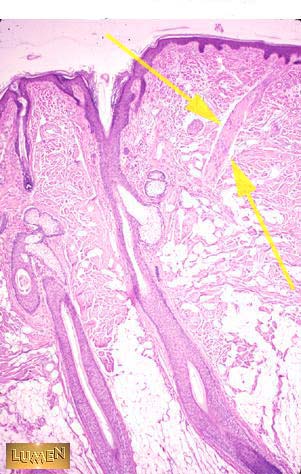

What is this structure?

Answer

Arrector pili muscle